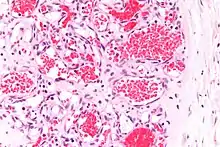

![]() | Granulation tissue | Micrograph showing proliferating capillaries, fibroblasts and acute inflammatory cells. | Category: Histopathology of granulation tissue | Granulation tissue |